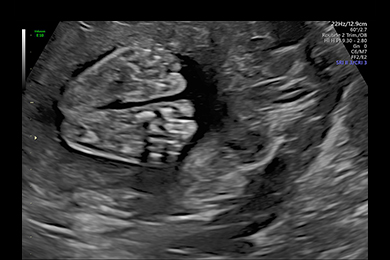

Gemini 13. SSW, Rückenansicht, 3D